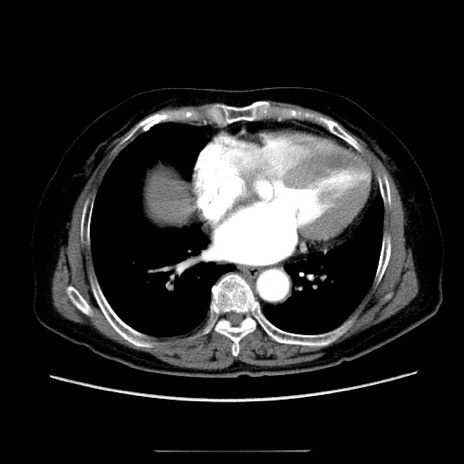

症例5(横断像)

【症例】70歳代女性

【主訴】お腹が張る

【現病歴】1週間くらい前から腹部膨満の自覚あり。昨日夜から増悪したため、本日救急外来受診。

【身体所見】意識清明、BT 36.5℃、BP 165/106mmHg、HR 80bpm、SpO2 98%、腹部:膨満、軟、自発痛・圧痛なし、触診にて不快感あり、腸蠕動音:減弱

【データ】WBC 12600、CRP 1.04